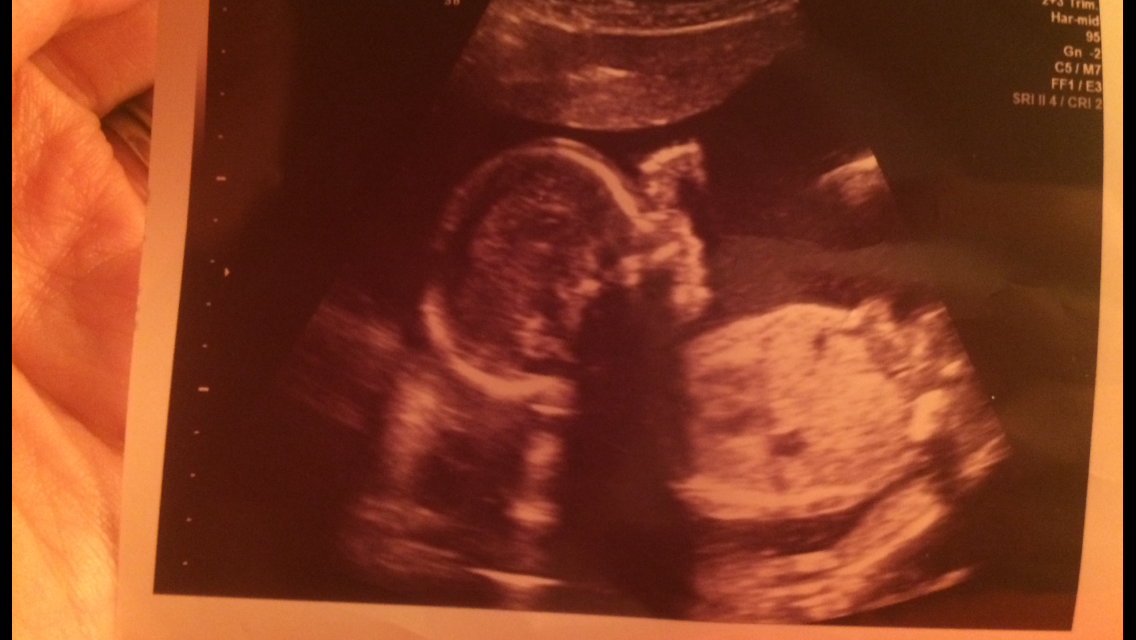

I love the 20-week scan! Baby clearly looks like a real baby and still all fits on the screen. We are team green, but baby's legs were crossed anyway (you can see the feet together at the top left). The tech also said he/she had its boxing gloves on because its hands were up by its face, but every once in a while the face would poke out. So much fun and super cute!